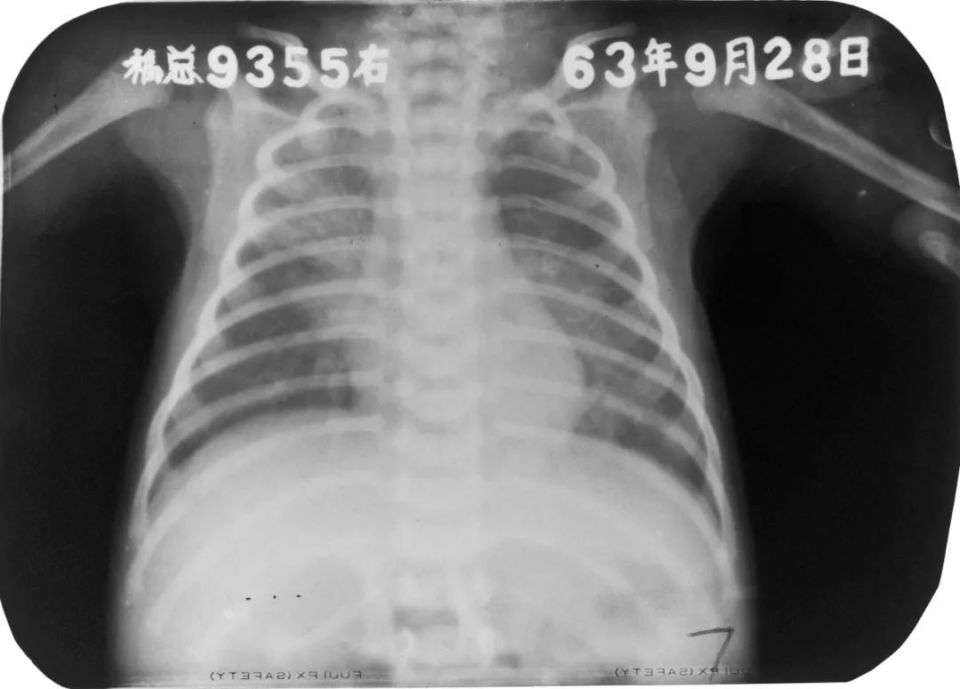

急性粟粒型肺结核(三均匀)

胸部正位片:两肺弥漫性分布大小不等的、分布均匀的粟粒状密度增高影,边缘模糊